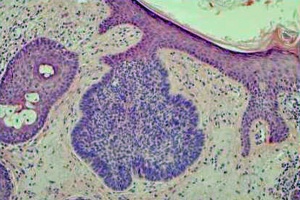

As its names implies, BCC derives from cells of the epithelial basal cell layer. Histologically the tumor has an appearance similar to the normal epithelial basal cell layer (Figure 1). BCC forms strands, cords, and islands of tumor. Palisading of the nuclei at the periphery of the islands of tumor is characteristic (Figure 1). An additional distinguishing feature of the tumor is the clefts or separation artifact, which results from tissue processing. Both nodular and morpheaform tumor growth types are seen in the periocular region.